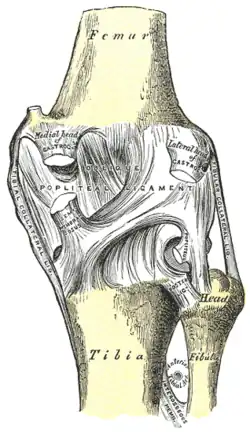

Hintere Bandsicherung

Auf der hinteren Seite des Kniegelenks finden sich zwei Bänder. Das schräge Kniekehlenband (Ligamentum popliteum obliquum) entspringt an der Ansatzstelle des halbhäutigen Muskels (Musculus semimembranosus) am inneren Schienbeinknorren und verstärkt die hintere Seite der Gelenkkapsel, mit der sie verschmilzt. Das bogenförmige Kniekehlenband (Ligamentum popliteum arcuatum) hingegen zieht vom hinteren Wadenbeinkopf über den Ansatz des Kniekehlenmuskels hinweg und zieht ebenfalls als Verstärker der Kapsel mittig nach oben.

Zentrale Bandsicherung

Die Kreuzbänder (Ligamenta cruciata) ziehen von der Grube zwischen den Oberschenkelknorren zum Schienbein. Von der Seite und von vorn betrachtet überkreuzen sie sich dabei in ihrem Verlauf.

Indem die Kreuzbänder ein verschobenes Abgleiten der Gelenkflächen nach vorn oder hinten (Translation) verhindern, stabilisieren sie das Knie. Zusätzlich hemmen sie die Drehbewegung, vor allem die Einwärtsdrehung, bei der sie sich umeinander wickeln und das vordere Kreuzband sich spannt. Bei der Auswärtsdrehung wickeln sie sich auseinander, wodurch das Knie bei maximaler Streckung immer ein wenig nach außen gedreht wird (Schlussrotation). Die klassische Verletzung des vorderen Kreuzbandes tritt daher, z. B. beim Skifahren, bei gebeugtem Knie und Einwärtsdrehung unter Gewalteinwirkung auf.

Eine Besonderheit ergibt sich durch die Lage der Kreuzbänder zur Gelenkkapsel. Sie liegen zwar innerhalb der äußeren Schicht der Gelenkkapsel (intrakapsulär), jedoch außerhalb der Innenhaut. Diese spart die Kreuzbänder nach hinten offen scharf U-förmig aus. Somit liegen sie außerhalb der eigentlichen Gelenkhöhle (extraartikulär). Diese Tatsache lässt sich entwicklungsgeschichtlich dadurch erklären, dass die Kreuzbänder während der Evolution von hinten eingewandert sind und dabei die Kapsel-Innenhaut mit nach vorne geschoben haben.

Bei isolierter Verletzung eines der beiden Kreuzbänder tritt das „Schubladenphänomen“ auf: Bei einem kompletten Riss (Ruptur) des vorderen Kreuzbandes lässt sich das Schienbein gegenüber dem Oberschenkelknochen weiter nach vorne verschieben als das unverletzte Knie, bei einem Riss des hinteren Kreuzbandes entsprechend nach hinten.

Vorderes Kreuzband

Das vordere Kreuzband (Ligamentum cruciatum anterius – bei Tieren Ligamentum cruciatum craniale) zieht von der vorderen Einmuldung zwischen den Schienbeinknorren zur Seite und etwas nach hinten, um an der Innenseite des seitlichen Oberschenkelknochens anzusetzen. Dabei teilt es sich in ein vorne-mittiges und in ein hinten-seitliches Bündel auf. Durch die weite Fächerung der Ursprungsfläche dieser Bündel ist sowohl bei Beugung, als auch bei Streckung ein Teil des vorderen Kreuzbandes gespannt. Dadurch verhindert es bei ausgestrecktem Bein eine Überstreckung (Hyperextension), während es bei Beugung dem Vorschub des Schienbeines entgegenwirkt („vordere Schublade“).

Hinteres Kreuzband

Das hintere Kreuzband (Ligamentum cruciatum posterius – bei Tieren Ligamentum cruciatum caudale) ist kräftiger und hat seinen Ursprung in der hinteren Einmuldung des Schienbeinplateaus und zieht nach vorne-mittig, um an der seitlichen Vorderfläche des inneren Oberschenkelknochens anzusetzen. Es spannt sich bei Beugung und verhindert damit ein nach hinten gerichtetes Weggleiten des Schienbeines (hintere Schublade). Bei ausgestrecktem Bein unterstützt das hintere Kreuzband das vordere beim Vorbeugen einer Überstreckung. Seine Hauptaufgabe ist jedoch die Stabilisierung des Knies bei Beugung und unter Last.